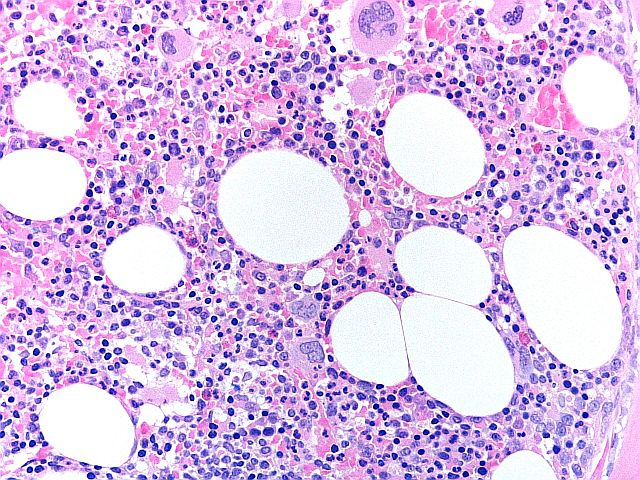

H+E - BMT Scheme

Seen at x20. Overall a very good preperation, but marks were deducted for folds and creases, loss of material, and haematoxylin background staining. This slide scored 8/10.